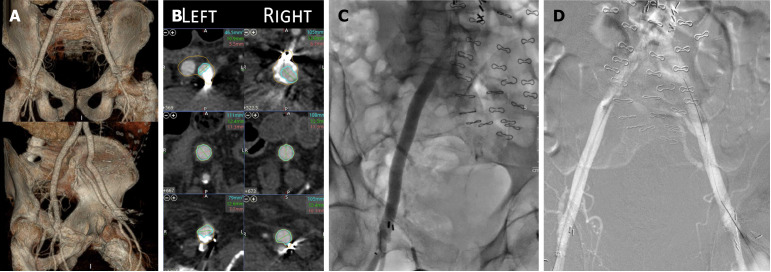

Case summary: An 82-year-old man presented with dyspnea on exertion. Echocardiogram was significant for severe aortic stenosis. Following a heart team discussion, the patient was scheduled for a balloon valvuloplasty followed by staged TAVR. Based on pre-TAVR computed tomography angiogram, the aortobifemoral graft was deemed as an appropriate access site. Micropuncture needle was used to access the right femoral artery graft, and the sheath was upscaled to 10 Fr. He underwent successful intervention to ostial left anterior descending and left circumflex arteries, and BAV with 22 mm Vida BAV balloon. Hemostasis was achieved using Perclose. For TAVR, an 8 Fr sheath was inserted via the right femoral bypass graft. The arteriotomy was pre-closed with two Perclose ProGlides and access was upsized to 18F Gore DrySeal. A 5Fr sheath was used for left femoral bypass graft access. Patient underwent successful TAVR with 29 mm CoreValve. Hemostasis was successfully achieved using 2 Perclose for right access site and one Perclose for left side with no postoperative bleeding complications.